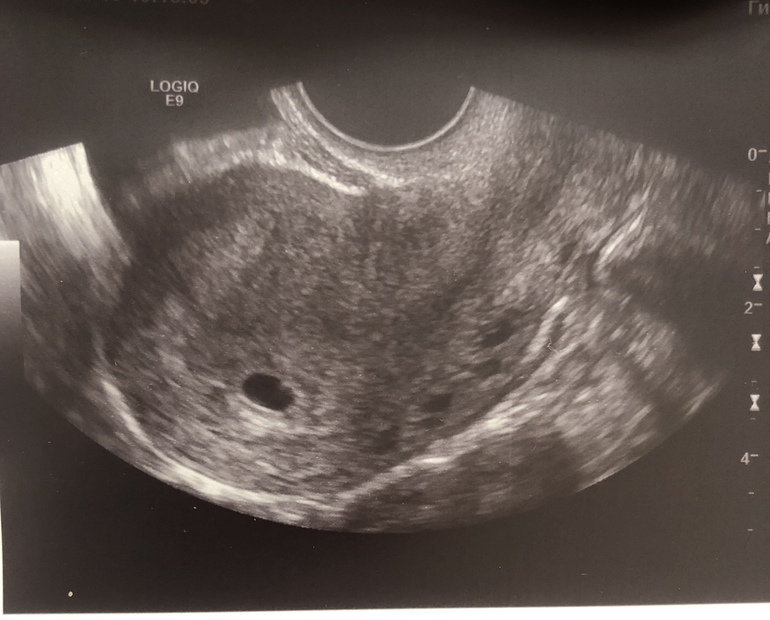

УЗИ 21 дпо

Беременность- 1 триместр ( только до 10 недель)Привет всем!) сегодня решила сходить на узи(5 нед 3 дня).

Нашли плодное яйцо😍, но эмбриончика ещё не видно(

Через две недели сказали придти и уже должно быть слышно сердечко)

Куда смотреть? Вот в этом черном пятне что то сбоку? Или куда?)))